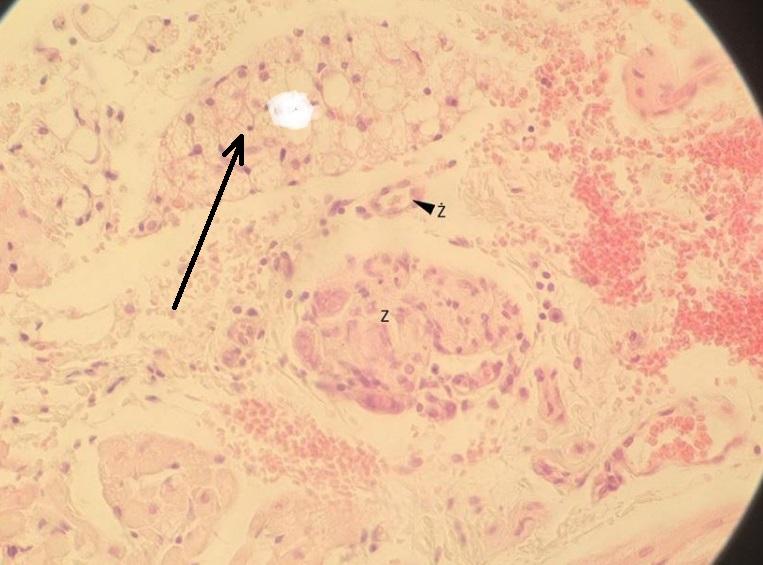

Pytanie 141

mięsień gładki napinający włos (skóra cienka)